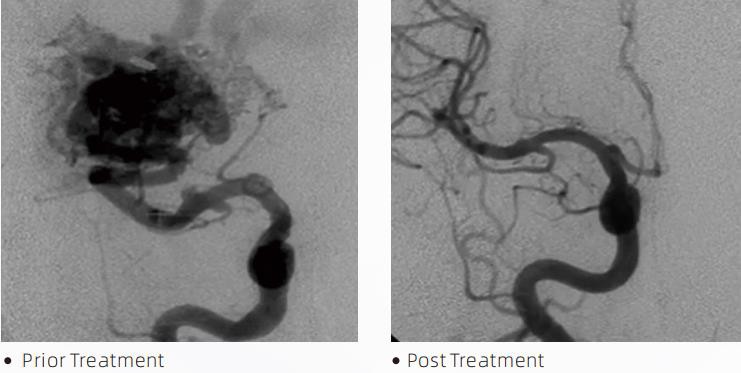

ลาวาตมLiquid Embolic System คือการบำบัดด้วยการสอดสายสวนเพื่อรักษาความผิดปกติของหลอดเลือดสมอง ความผิดปกติของหลอดเลือดสมองหมายถึงกลุ่มของความผิดปกติของหลอดเลือดในระบบประสาทที่ไม่ร้ายแรงหรือร้ายแรง ซึ่งสามารถนำไปสู่การตกเลือดในกะโหลกศีรษะ ภาวะสมองตาย ภาวะสมองขาดเลือด และโรคอื่นๆ ระบบการ embolization ของเหลวเป็นอุปกรณ์ทางการแพทย์ที่ดำเนินการโดยการใส่ของเหลวภายในหลอดเลือดอย่างง่าย ซึ่งจะ embolizes หลอดเลือดในสมองที่ผิดปกติโดยการฉีดวัสดุของเหลวพิเศษ วัสดุของเหลวจะก่อให้เกิดการอุดตันของเนื้อเยื่อที่ควบคุมภายในหลอดเลือด ซึ่งสามารถลดผลกระทบของความผิดปกติของหลอดเลือดสมองต่อผู้ป่วยได้ สายสวนขนาดเล็กสำหรับนำส่งที่เข้ากันได้กับ DMSO ซึ่งระบุไว้เพื่อใช้ในหลอดเลือดสมองใช้เพื่อเข้าถึงตำแหน่งที่เส้นเลือดอุดตัน สารอุดเส้นเลือดลาวาเป็นระบบสารช่วยอุดตันของเหลวแบบไม่ยึดติด ประกอบด้วยโคโพลีเมอร์ EVOH (เอทิลีนไวนิลแอลกอฮอล์) ที่ละลายใน DMSO (ไดเมทิลซัลฟอกไซด์) และผงแทนทาลัมขนาดไมครอนแขวนลอยเพื่อให้เกิดความแตกต่างในการมองเห็นภายใต้การส่องกล้อง ลาวาตมมีจำหน่ายในสามสูตรผลิตภัณฑ์ LAVA-12 LAVA-18 และ LAVA-34 LAVA-12: แนะนำเมื่อป้อนภาชนะขนาดเล็กส่วนปลายและผ่านเครื่องป้อนขนาดเล็ก ลาวา-18: แนะนำเมื่อให้อาหารโดยการฉีดหัวขั้วใกล้กับโพรงจมูก LAVA-34: แนะนำสำหรับการรวมการไหลที่สูงขึ้นและส่วนประกอบที่มีรายละเอียดมากขึ้น